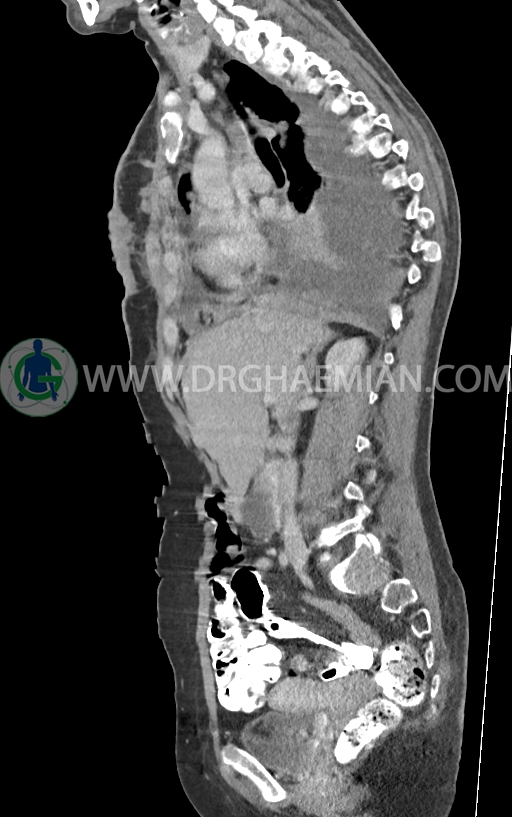

در سی تی اسکن اسپیرال ریه و مدیاستن -شکم و لگن با کنتراست خوراکی و وریدی (مولتی دیدکتور 16 با مقاطع ظریف و بازسازی های ساژیتال و کرونال) :

–ضایعات استخوانی لیتیک فراوان منتشر در تمامی طول ستون مهره و لگن رویت شدند که مطرح کننده متاستاز استخوانی می باشند.

–شکستگی پاتولوژیک در مهره های T6 , T10 , T11

–کیفوز موضعی در Level T10 , T11 در ستون مهره

–رتروپالشن شکستگی مهره T10 همراه با ایجاد تنگی کانال نخاعی

–ضایعه استخوانی لیتیک کوچک همراه با شکستگی در قوس خلفی دنده 11 راست (متاستاز استخوانی)

–متاستاز استخوانی در قوس خلفی دنده 8 راست

–خط لوسنت مشکوک برای شکستگی در قوس خلفی دنده 8 راست و قوس خلفی دنده 7 چپ

مشهود است.